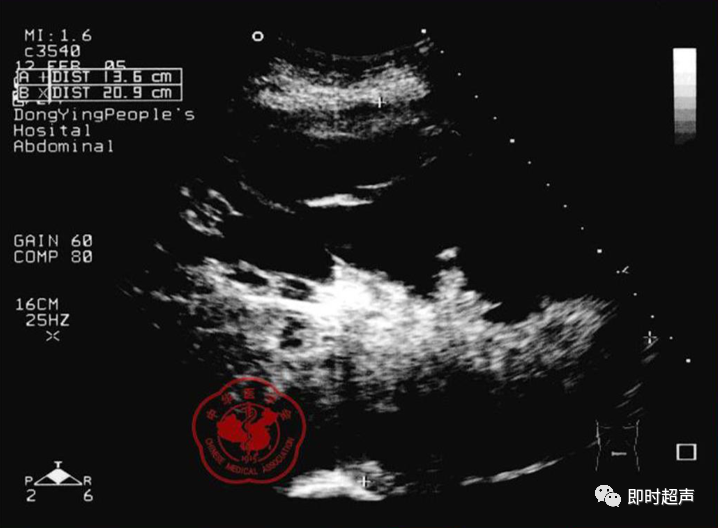

• GIST的发病机制与KIT信号通路的激活有关。• KIT是一种酪胺酸激酶跨膜受体蛋白,未经“装配”过的KIT蛋白是一种非活化的单体,参与细胞膜形成。几乎所有GIST都表达了KIT蛋白,而且大多突变的KIT基因保留了表达KIT蛋白的特性。c-kit内的突变主要见于恶性病例,特别是外显子11的点突变,还有外显子9、13和17,可以导致本质的或配体独立的c-kit激活,引发细胞的无序增殖和凋亡。这些具有功能的突变是GIST发病机理的关键,并且与肿瘤的恶性程度和预后较差相关。• GIST约75%发生于50岁以上老年人,中位年龄为58岁,无明显差异。• 可以发生在消化道从食道到肛门的任何部位,偶尔可原发于网膜、肠系膜和腹膜后,约50%发生在胃,25%发生在小肠,不足10%发生于食管、结肠及直肠。大体观察:肿块多境界清楚,类圆形,结节状,部分有假包膜。切面灰白、灰红,质韧,部分质嫩呈鱼肉状,伴有出血、坏死、囊性变。• 肿瘤组织主要由两种细胞组成,一种为长梭形细胞,细胞质丰富,嗜酸性,细胞核呈梭形或杆状;另一种为上皮样圆形或多角形细胞,细胞肥胖,胞质少。两种瘤细胞常呈束状、编织状或旋涡状排列。• 部分病例细胞异型明显,核分裂象增多,可见病理性核分裂象和瘤巨细胞。梭形细胞界不清楚,胞质丰富,淡染,轻度嗜伊红或略嗜碱,可有纤细、长梭形、短梭形或胖梭形、卵圆形,可见核仁。细胞核两端钝圆,部分病例胞质呈空泡状,位于核一端形成核端空泡胞,多呈交叉束状、旋涡状、席纹状及栅栏状排列。上皮样细胞胞浆丰富或透亮,多呈弥漫片状、束状或巢状排列。肿瘤间质可有出血、囊性变、坏死及黏液变,可见炎性细胞浸润。CD34抗原是一种115kd的糖基化蛋白,50%~80% GIST的CD34表达为阳性,CD34对鉴别GIST和典型的平滑肌瘤,神经鞘瘤还是非常有用的标记物,因后两者的CD34一般是阴性的。但CD34在诊断GIST上其特异性受到限制,一般情况下CD34多与CD117联合应用,方能提高GIST的诊断率。• 与肿瘤大小、发生部位、肿物与肠壁的关系以及肿瘤的良恶性有关。• 肿瘤较小者(直径小于2cm)常无症状,往往在体检和其它手术时无意中发现。• 肿瘤发生于胃肠道腔内时大多表现为呕吐、腹痛及消化道出血,而发生于胃肠道腔外的则主要表现为腹部包块。• 最常见的临床症状是中上腹部不适、腹部肿块及便血。• 对于临床发现的消化道(包括肠系膜、网膜、后腹膜)实体肿瘤,在排除其他常见肿瘤后,才考虑GIST。目前,诊断GIST有三条标准:③肿瘤组织具有梭形细胞和上皮样细胞两种基本细胞成分的病理学特征。这是诊断GIST金标准。CD117阳性者或CD117阴性而CD34阳性者,且伴平滑肌和神经双向分化或无分化者,可诊断为GISTs;以Desmin和SMA强阳性,而CD117阴性诊断为平滑肌肿瘤;以S-100阳性,CD117、Desmin、SMA均阴性诊断为神经鞘瘤。• GISTs的分型与组织学良恶性的关系:研究证实GISTs非单一分化的肿瘤,具有多向分化。• 当前GISTs的良性、交界性和恶性判断标准多参照Amin等提出的标准:②交界性:核分裂<5/50HPF,但肿瘤>5cm;• 另外研究显示,平滑肌型大多数为良性,少数为交界性和恶性,神经源型为恶性,双向分化亚型和未分化型为交界性和恶性,提示GISTs的分化型与其良恶性之间有一定关系。• 胃间质瘤早期多局部侵犯,后期出现肝转移和腹腔内种植,小肠间质瘤早期即可出现转移• 主要有超声扫描(检出率30%左右)、纤维内镜、超声内镜、CT、MRI、普通X• 线检查(胃肠钡餐造影、小肠插管气钡双重造影)、选择性血管造影检查等。• 不同部位的GIST,各种检查方法的敏感性不同。以CT检查为佳,尤其是螺旋CT,分辨率最高,可以三维重建,直接显示肿瘤大小、形态、密度、内部结构、边界,对邻近组织的侵犯也看得很清楚,同时还可观察其他部位的转移灶,有利于分期、鉴别与诊断。• MRI具有多轴成像及反映肿瘤内部成分的优点,尤其是动态扫描及各种新的扫描系列的出现更使其可以普及应用。• DSA检查对于GIST,特别是有消化道出血的患者更有价值。• 上述影像学检查表现并非特异性,与胃肠道平滑肌肿瘤、神经源性肿瘤鉴别困难。明确诊断要依赖病理免疫组化等手段。• 超声图像特征 肿物体积较小者(直径< 5. 0 cm )多为实性病变, 呈类圆形, 边界清晰, 内部回声多为较均匀的低回声。• 肿物体积较大者(直径> 5. 0 cm ) 多为混合性病变,呈不规则圆形或分叶状, 多数边界尚清晰, 以实性为主的病变内部为不均质中低回声伴不规则液性区及斑点状强回声; 以囊性为主的病变囊壁较厚,有分隔, 部分囊腔内可见点状、团状低回声。CDFI显示肿物实质回声内血流均较丰富。病例1:患者男, 62岁。自扪腹部包块2月余,包块增大20天就诊。查体:腹部平坦,无腹壁静脉曲张,无胃肠型及蠕动波,腹肌软,剑突下5cm处及左肋缘下可触及一质韧包块,大小约15*12cm,活动度差,边界尚清,包块深压痛,全腹无反跳痛。化验检查AFP:3.66(1.09-8.04)ng/ml,CEA:2.85(0-5)ng/ml。体格检查:一般情况良好,全腹软、平坦,腹部无压痛。超声检查:患者仰卧位时左上腹于胰尾前方可见一大小约6. 1 cm ×5. 8 cm ×5. 3 cm实性均质低回声,形态规则,包膜完整,边界清晰,活动度大;右侧卧时,肿块移至胰头右前方(图1) ;于其内探及丰富血流信号。体格检查:一般情况良好,腹丰满,上腹部有轻压痛,未扪及明显肿块。超声检查:患者仰卧位时左上腹于胰尾前方、脾门处可见一大小约10. 0 cm×8. 8 cm×7. 6 cm 实性低回声(图2) ,形态规则,包膜完整,边界清晰,肿块活动度大;右侧卧时,肿块移至左肝下间隙,回声尚均质;于其内探及较丰富血流信号(图3) 。图3 腹腔低回声肿块位于左肝下间隙,于低回声肿块内探及较丰富血流信号向壁外生长的胃肠道间质瘤, st为胃腔,箭头所指为胃壁, T为向外生的肿瘤• 胃间质瘤的定位准确率要高于十二指肠及小肠间质瘤,这主要是因为胃的解剖位置相对固定,且通过饮水使胃腔充盈,可清晰的显示胃壁的各层结构及肿块与胃壁的关系。肿块多表现为粘膜下、肌层或浆膜下低至中等回声团块,可向腔内、腔外或腔内外生长。但当肿瘤较大或浸润周围脏器时,超声定位仍有困难, 因此,超声如发现上腹部肿块且怀疑来源于胃者,应尽可能嘱其饮水充盈胃腔,并多角度、多切面观察肿块与周围脏器的关系,以提高定位的准确性。• 十二指肠间质瘤的定位亦较准确,但降部的外生性肿块常与胰头粘连而误诊为胰腺肿瘤回声均匀且位置较深的间质瘤亦可能误为胰头周围淋巴结。• 空、回肠间质瘤常因肿块较大,多发,位置不固定而难以定位,往往误诊为腹、盆腔或腹膜后肿瘤,超声检查如发现肿块局部肠壁增厚,肿块与肠道随呼吸同步运动时可作出定位诊断。• GIST的声像图表现有助于其良、恶性的鉴别:良性肿瘤多体积较小,圆形或椭圆形,回声均匀,边界清晰。恶性肿瘤多较大,呈不规则分叶状,回声不均匀,内部易出血、坏死、囊变。• 肿瘤长径与肿瘤内部是否出现无回声区在良、恶性病变之间的差异有统计学意义,是判断良恶性的有效征象。• 如以肿瘤长径>5cm为诊断恶性标准,其敏感性、特异性及准确性均较理想。超声可为临床提供胃肠道间质瘤的部位、大小、边界、回声等较多有用信息,一部分病例可作出定位、定性诊断,并可在术后或复发患者药物治疗期间对其进行动态观察;CDFI方便快捷、无需造影剂即可对间质瘤周边及内部血流进行观察,可为临床医师提供肿瘤血供情况。但未发现腹腔或肝脏转移时,超声判断胃肠道间质瘤性质有一定难度。• 目前临床上对GISTs的治疗效果并不十分满意。治疗仍以手术为主,对无法手术切除或已有转移的GISTs患者进行甲磺酸伊马替尼化疗。• 手术方式取决于肿瘤大小、部位和术中冰冻切片结果等。• 发生在胃的间质瘤,可首选胃大部切除术;发生在十二指肠的间质瘤可行保留胰头的十二指肠切除术或胰十二指肠切除术;发生在小肠的间质瘤可行肿瘤肠段切除术;发生于结肠的间质瘤可行左半或右半结肠切除术;发生于直肠的间质瘤可行肿瘤局部切除术。一般情况下无需淋巴结清扫。• 术后随访监测,复发者单个病灶可考虑手术切除;多发或转移特征者应试行甲磺酸伊马替尼化疗,并监测肿瘤大小及数目的改变。• 随着分子靶点药物进入肿瘤临床,一种小分子化合物———酪胺酸激酶受体抑制剂,美国称为Gleevec,欧洲叫做Glivec(格列卫),在治疗GIST和慢性粒细胞白血病方面有其独特的作用。已知细胞膜表面上皮生长因子受体酪胺酸激酶抑制剂大致分为两大类:一类是小分子化合物;另一类是特异性抗体。利用抑制酪胺酸激酶的活性,对处于增殖期状态的病变具有治疗的作用。Glivec在体外、体内和细胞水平都可强烈抑制酪胺酸激酶的活性,是干细胞因子(SDCF)受体KIT的强抑制剂。• Glivec推荐用量为400mg(4片),每日一次, 3个月为一疗程。如服3个月后无效可加至600mg/d~800mg/d(6~8片)[18];若仍无效果不再增量应停止治疗。• Glivec治疗进展转移的GIST总有效率为50%左右,比传统化疗有效率高十倍以上;肿瘤生长控制率达80%以上,起效最快在服药后24h之内,使症状改善如疼痛缓解;平均起效时间为13周(约3个月)。患者体力状况改善是又一突出效果。2/3患者治疗后无症状可如健康人生活工作。• Brainard等研究发现间质瘤预后差的前两位因素为肿瘤大小和核分裂象,故对于间质瘤直径>5cm和核分裂象>5/50HPF的患者应给予口服Glivec。最近,Liu报道口服Glivec治疗可使85%患者的病情得到控制。